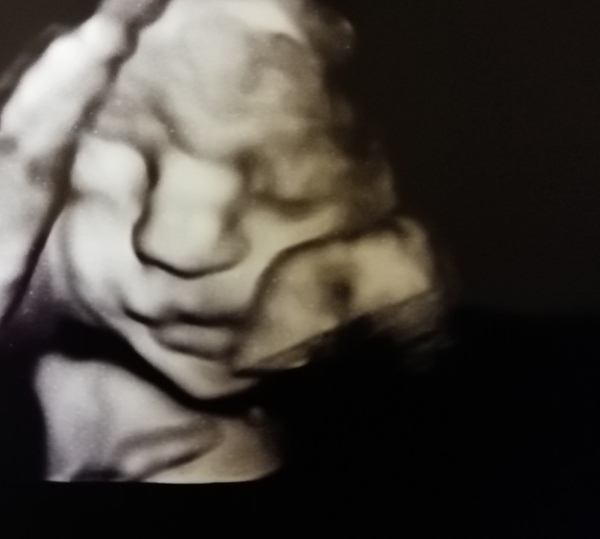

What a lovely scan photo!! Really glad it was a reassuring appointment. Great news.